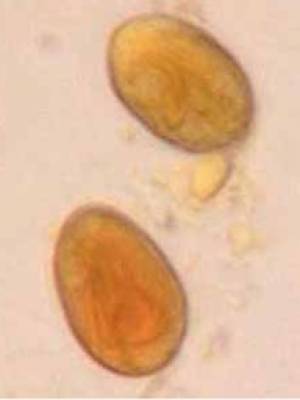

- Protozoen

- Kokzidien

- Isospora spp.

- Kotflotation

- Indikation: Würmer, Giardien, Kokzidien

- Durchführung: Flotation in Zinksulfatlösung mit darüber liegendem Deckglas für 10 Minuten

- Sammelkotproben wesentlich aussagekräftiger, da Wurmeiern intermittierend ausgeschieden werden